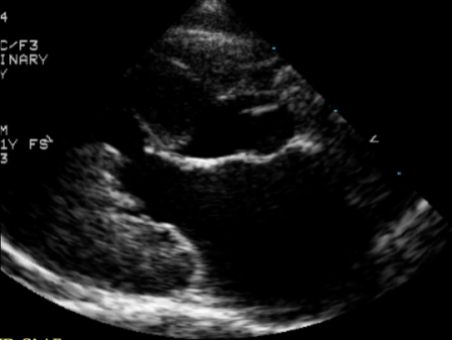

Khi mèo bị HCM nặng, siêu âm tim thường rõ ràng các dấu hiệu như: dày thành thất trái khu trú hoặc toàn bộ, cơ nhú phì đại nặng, hiện tượng SAM, mất khoang thất trái kỳ tâm thu, giãn nhĩ trái mức độ nhẹ đến nặng.

Dày thành thất trái MC cây nấm

Ở mèo, dày thành thất trái đối xứng thường xảy ra hơn. Phát hiện siêu âm tim phổ biến ở mèo là hiện tượng lồi vách liên thất ở đáy tim. Hiện tượng này thường thấy đơn lẻ, hoặc có thể thấy ở mèo bị dày các vùng khác của thất trái. Nhiều con mèo có hiện tượng lồi vách liên thất ở đáy tim, nhưng không tiến triển ở các vùng khác, điều này gây khó khăn trong chẩn đoán. Phần lồi này thường gây hẹp đường ra thất trái (LVOT) tạo ra hiện tượng SAM ở mèo.

Lồi vách liên thất

SAM và dày thành thất trái